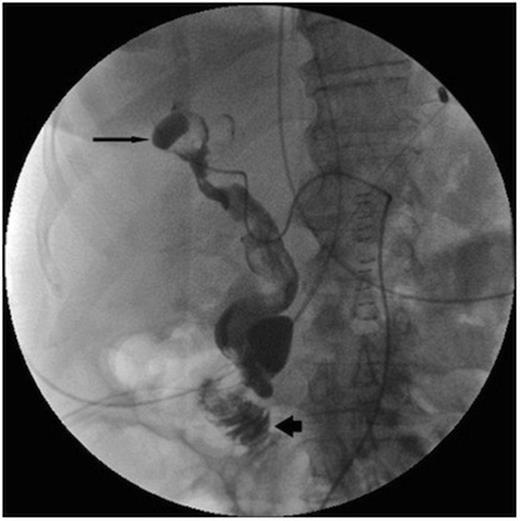

Post operatively the upper gastrointestinal bleeding continued. A second urgent OGD endoscopy showed more blood clots and fresh blood in the fundus, but once again no source for the bleeding was seen. Once the patient was stabilised an angiogram was performed. This showed a 1cm pseudoaneurysm of the right hepatic artery in the right lobe close to the Porta Hepatis. The pseudoaneurysm arose from the anterior branch of the right hepatic artery and communicated with the bile duct. The 2nd part of the duodenum was opacified, showing haemorrhage from the lesion into the duodenum via the bile duct (Figure 1).

Initially, selective embolisation of the anterior right hepatic artery was performed using small coils (COOK UK) and small particles of grated gelatin sponge soaked in 0.5ml of 5% Ethanolamine. However this proved to be ineffective (Figure 2), and so the posterior branch of the right hepatic artery was embolised, successfully controlling the haemobilia. The left hepatic artery was spared.